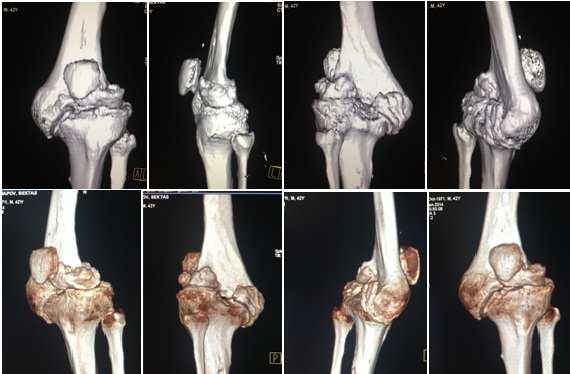

Для диагностики гонартроза применяются рентгенография коленного сустава и лабораторные анализы крови. Увеличение скорости оседания эритроцитов (СОЭ) указывает на воспалительный процесс в организме. Рентгеновские снимки помогают выявить изменения в суставе и определить стадию заболевания.

Процесс сопровождается выраженными болевыми ощущениями, которые трудно игнорировать. Боли становятся постоянными и могут проявляться не только при движении, но и в состоянии покоя, усиливаясь утром и вечером. Движения затруднены и замедлены, в колене могут возникать резкие хрустящие звуки или щелчки, наблюдается деформация, а при ощупывании возникают болезненные ощущения. На рентгеновских снимках видно значительное сужение суставной щели, деформацию сустава и костей, а также осложнения в виде разросшихся остеофитов.

Тяжелая (3 степень). На этой стадии изменения в суставе становятся необратимыми. Под разрушенным хрящом начинает проявляться кость, в которой нарушается кровообращение. Избыточное количество синовиальной жидкости приводит к изменению формы колена. Ситуацию усугубляют сильно разросшиеся остеофиты, которые становятся дополнительным фактором деформации.

Эта стадия характеризуется невыносимой постоянной болью. Либо движения сустава ограничены, либо он становится полностью неподвижным. Ходьба становится практически невозможной. На рентгеновских снимках видны разросшиеся остеофиты, стертая хрящевая ткань, а также разрушенные мениски и связки.